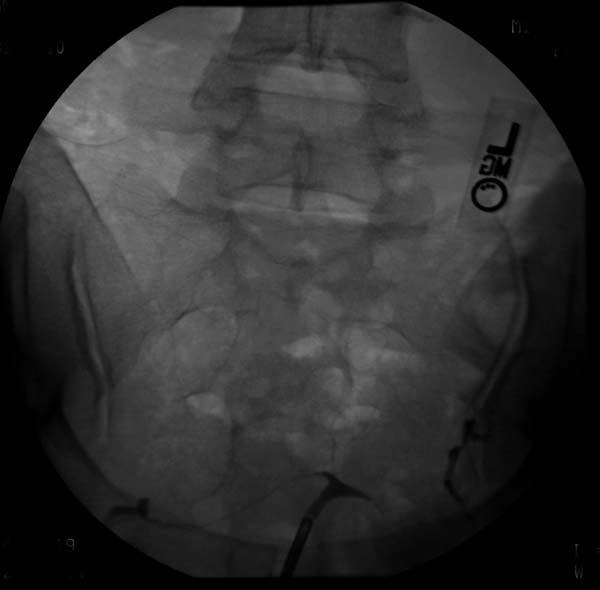

자궁 기형은 여성의 자궁 구조에 이상이 있는 상태를 의미하며, 일반 인구의 약 6.7%에서 나타난다. 미국생식의학회(ASRM)는 자궁 기형을 뮐러관 무발생, 단각 자궁, 중복 자궁, 쌍각 자궁, 자궁 중격, DES 자궁 등 6가지 유형으로 분류한다. 진단은 초음파, MRI, 자궁난관조영술 등의 영상 기술을 통해 이루어지며, 자궁 중격과 같은 특정 기형은 수술로 치료할 수 있다.

신체 검사 외에도 의사는 기형의 정확한 특징을 파악하기 위해 영상 기술을 활용한다. 주로 사용되는 영상 기술에는 부인과 초음파 검사, 골반 MRI, 또는 자궁난관조영술이 있다. 하지만 자궁난관조영술은 자궁의 외부 윤곽을 평가하기 어렵고, 쌍각 자궁과 중격 자궁을 구별할 수 없다는 한계 때문에 유용성이 떨어진다고 여겨진다.